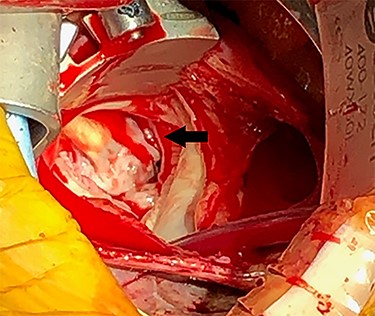

Eight months after MitraClip implantation, the patient underwent MV replacement via a minimally invasive right thoracotomy. The patient underwent cardiopulmonary bypass via the femoral vessels. Through a right thoracotomy, a left atriotomy was made. The previously placed mitral clips were associated with fibrotic changes and damage to the leaflets (Figs 2 and 3). The left ventricle was noted to be severely dilated. The MV was replaced with a 25-mm bovine pericardial bioprosthesis. Cardiopulmonary bypass was terminated at the conclusion of the operation with moderate inotropic support and satisfactory hemodynamic parameters. The intraoperative transesophageal echocardiogram showed mild improvement of LVEF from 20 to 30%. The bioprosthetic mitral valve was functioning appropriately without para-valvular leak and a transvalvular gradient of <2 mmHg. Postoperative transthoracic echocardiogram revealed an LVEF 30–35% and a normally functioning bioprosthetic MV with a mean transmitral gradient of 5 mmHg. The patient was extubated, weaned off inotropic support, and transferred out of the intensive care unit on post-operative days two, four and seven, respectively. She was ultimately discharged to home with home services. Her echocardiogram remained stable at time of discharge and 1 month follow-up. At 6 months postoperatively, the patient continued to progress with one brief hospital admission for non–cardiac-related concern.

(A) Echocardiogram showing mitral clip (white arrow) at 4 months after clip placement; (B) at 7 months, left ventricular ejection fraction was 15–20%, diastolic and systolic diameters were 54 and 51 mm, respectively, and mean transmitral gradient 2.1 mmHg.